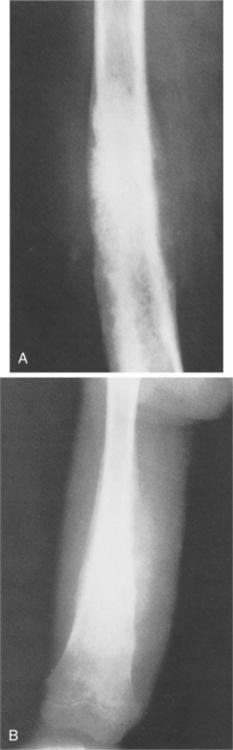

Those found in the long bones are usually in the diaphysis, although as with most tumors, they can be seen elsewhere (Fig. 26-5). The histologic makeup of osteoblastoma is very similar to that of an osteoid osteoma. In fact, sometimes it is size alone that differentiates the two, with osteoblastoma being the larger. The lesions are osteolytic and have a sclerotic border.

Figure 26-5 Genuine (conventional) osteoblastoma of the tibia in a 24-year-old woman. Anteroposterior (A) and lateral (B) radiographs show a round radiolucent lesion with slightly sclerotic borders at the lower and anterior aspect of the tibia. (From Gitelis S, Schajowicz F: Osteoid osteoma and osteoblastoma, Orthop Clin 20:320, 1989.)